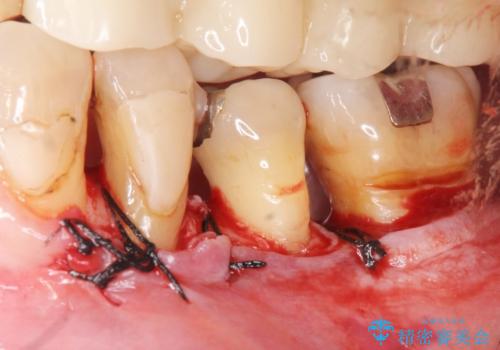

骨吸収の進行している左下臼歯部に、再生療法(骨を増やす手術))を行いました。

再生療法から1年後、リエントリー手術により骨の再生を確認し、骨外科処置(骨を平らにして歯周ポケットの根本的な改善を図る処置)を行いました。

再生療法と骨外科処置により、歯周ポケットは全周2mm以下となりました。